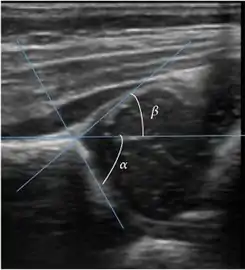

Ultrasound allows categorizing pediatric hips, according to Graf’s criteria, in four main types: normal, immature, and dysplastic (subluxed and dislocated). This classification is based on measurements of the acetabular inclination angle (alpha), cartilage roof angle (beta), and infant age. The femoral head coverage can also be determined by dividing the length of the femoral head covered by the acetabular fossa and the diameter of the femoral head. Its lower normal limits are 47% for boys and 44% for girls (Figure 11).[1]

Figure 11:

Useful ultrasound measures in neonatal hip sonography, alpha and beta angles.[1]

Measurement of femoral head coverage.[1]